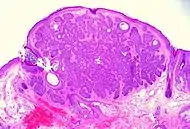

Basal-cell carcinoma cells appear similar to epidermal basal cells, and are usually well differentiated.[19]

Nodular basal-cell carcinoma (also known as "classic basal-cell carcinoma") accounts for 50% of all BCC.[21] It most commonly occurs on the sun-exposed areas of the head and neck.[22]:748[23]:646 Histopathology shows aggregates of basaloid cells with well-defined borders, showing a peripheral palisading of cells and one or more typical clefts.[21] Such clefts are caused by shrinkage of mucin during tissue fixation and staining.[24] Central necrosis with eosinophilic, granular features may be also present, as well as mucin. The heavy aggregates of mucin determine a cystic structure. Calcification may be also present, especially in long-standing lesions.[21] Mitotic activity is usually not so evident, but a high mitotic rate may be present in more aggressive lesions.[21] Adenoidal BCC can be classified as a variant of NBCC, characterized by basaloid cells with a reticulated configuration extending into the dermis.[21]

Cleft.